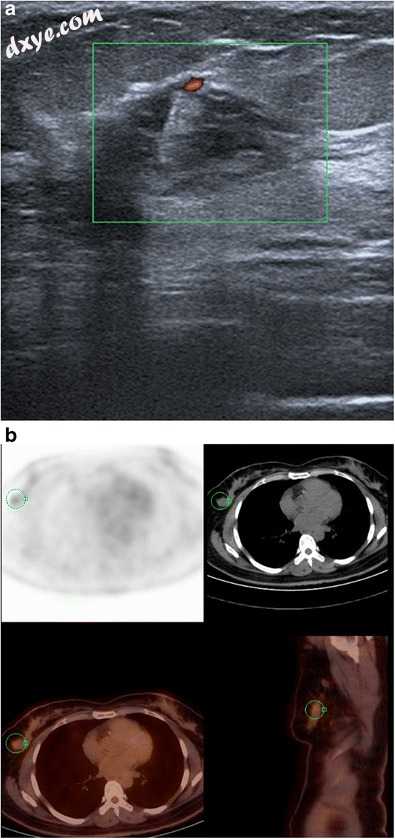

淋巴瘤

淋巴瘤通常在老年患者中观察到,通过局部炎症引起的疼痛,可触及的肿块显示,有时伴有可触及的腋窝淋巴结。乳房X线照相显示不规则或小叶非钙化肿块。多个肿块也可能导致不对称密度。超声通常显示或多或少界限良好,血管外,低回声肿块或有时混合回声肿块,伴有高回声周围(图19)。大约23%的乳腺淋巴瘤可见高回声和混合回声。一些作者认为,多普勒超声检查中高回声肿块中高血管化的存在证明了活检[7,22]。

图19

淋巴瘤。 右乳房的超声显示分界不良,混合回声肿块,多普勒超声检查血流。 b该患者的PET-CT扫描显示右侧乳房有一个代谢亢进的病变。 微生物学检查显示弥漫性大B细胞淋巴瘤